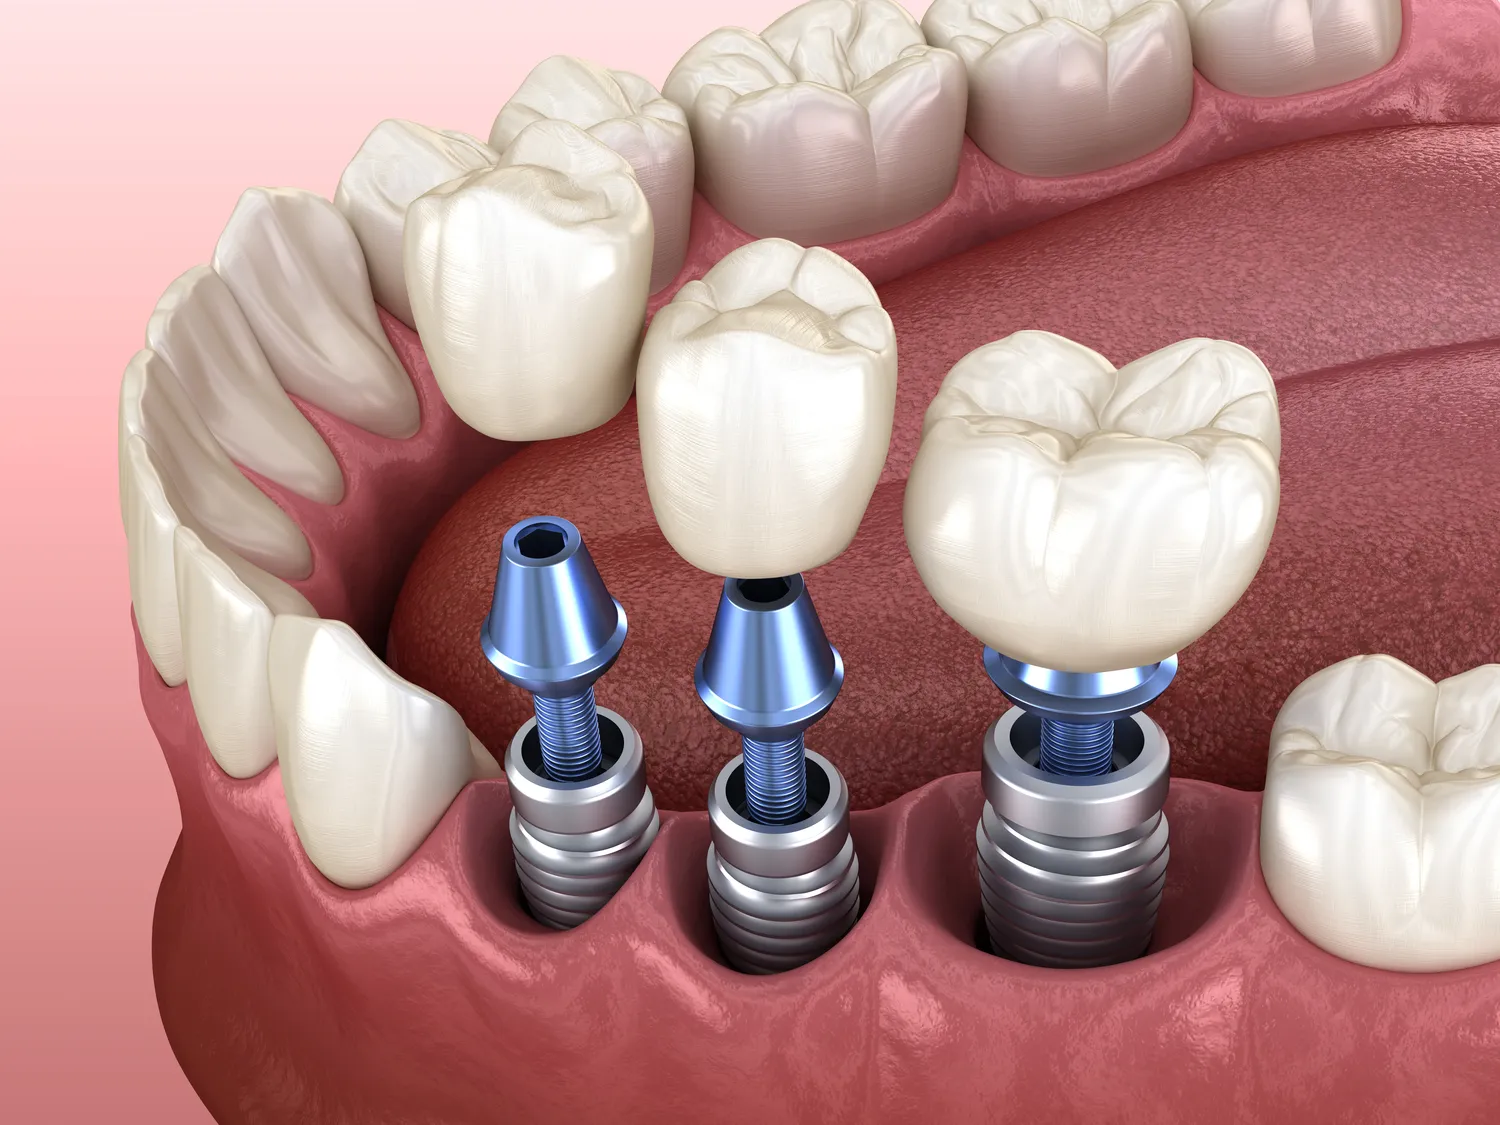

Bezśrubowe implanty to nowoczesne rozwiązanie w dziedzinie stomatologii i ortopedii, które zyskuje coraz większą popularność. Ich konstrukcja opiera się na innowacyjnych technologiach, które eliminują potrzebę stosowania tradycyjnych śrub do mocowania implantu w kości. Zamiast tego, bezśrubowe systemy wykorzystują mechanizmy osseointegracji oraz specjalnie zaprojektowane kształty implantów, które umożliwiają stabilne osadzenie się w tkance kostnej. Dzięki temu proces gojenia może być szybszy i mniej inwazyjny dla pacjenta. W przypadku stomatologii, bezśrubowe implanty są często stosowane jako zamiennik dla tradycyjnych rozwiązań protetycznych, co pozwala na uzyskanie lepszej estetyki oraz funkcjonalności zębów.

Proces wszczepiania bezśrubowych implantów jest zazwyczaj podobny do standardowego zabiegu zakupu tradycyjnych implantów dentystycznych lub ortopedycznych, jednak różni się kilkoma kluczowymi aspektami. Na początku przeprowadza się szczegółową diagnostykę obrazową, aby ocenić stan kości i ustalić optymalne miejsce na wszczepienie implantu. Następnie lekarz wykonuje niewielkie nacięcie w dziąśle lub skórze oraz przygotowuje odpowiednią przestrzeń w kości poprzez delikatne wiercenie lub modelowanie tkanki kostnej. Po tym etapie następuje umieszczenie implantu bez użycia śruby; cała procedura trwa zazwyczaj krócej niż przy zastosowaniu konwencjonalnych metod mocowania.

Bezśrubowe implanty to nowoczesne rozwiązanie w dziedzinie stomatologii oraz ortopedii, które eliminuje potrzebę stosowania tradycyjnych śrub mocujących. W przeciwieństwie do konwencjonalnych implantów, które wymagają dodatkowych elementów do stabilizacji, bezśrubowe implanty opierają się na innowacyjnej technologii opartej na precyzyjnych kształtach i materiałach. Te konstrukcje wykorzystują siły zgryzu oraz naturalne procesy biologiczne organizmu do uzyskania stabilności. Dzięki temu możliwe jest uniknięcie problemów związanych z luźnymi śrubami czy ich uszkodzeniem.

Produkcja bezśrubowych implantów opiera się na zaawansowanych materiałach biokompatybilnych, które zapewniają nie tylko trwałość, ale także bezpieczeństwo dla organizmu ludzkiego. Najczęściej wykorzystywane materiały to tytan oraz ceramika dentystyczna. Tytan charakteryzuje się doskonałą odpornością na korozję i dużą wytrzymałością mechaniczną, co czyni go idealnym materiałem dla elementów narażonych na znaczne obciążenia w trakcie codziennych czynności takich jak żucie czy gryzienie. Ceramika natomiast dostarcza estetycznych walorów końcowemu produktowi dzięki swojej zdolności do imitowania koloru naturalnych zębów.